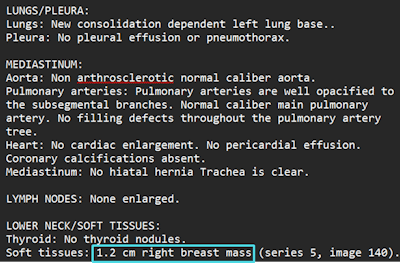

Onc.AI is a Series-A funded company that’s developing imaging AI models for predicting clinical outcomes in cancer patients, initially focusing on metastatic lung cancer.

The firm sells models directly to pharmaceutical companies such as Pfizer, GSK, and Amgen to inform drug development. It is also developing clinical models intended for medical oncology decision support.

AI predictions for treatment response in metastatic lung cancer patients are provided in a PDF format.Onc.ai

AI predictions for treatment response in metastatic lung cancer patients are provided in a PDF format.Onc.ai

“Although our AI models are solely based on a cancer patient’s CT or PET/CT scan, our main user is the medical oncologist,” said Akshay Nanduri, founder and CEO.

In January, Onc.ai received a breakthrough device designation from the U.S. Food and Drug Administration for its Onclara model for metastatic lung cancer; the software was previously known as Serial CT Response Score. The company hopes its first models will be cleared for marketing authorization as software-as-a-medical device (SaMD) decision-support software in the second half of 2026.